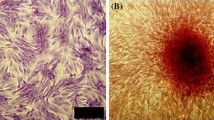

The isolation of bone marrow stromal cells and the culture of osteoblasts

Bone fragments containing bone marrow isolated from the posterior iliac crest of experimental animals were added to a container filled with 30 mL of 10% FBS––α MEM (Sigma Chemical Company, St. Louis, MO, USA) and 350 units of heparin, and were transported to the laboratory. After careful mixing, large bone fragments were removed, and the remaining mixture was centrifuged at 4 °C, 472g, for 10 min. The precipitate was treated with collagenase (Sigma) for 24 h, and centrifuged, after which the supernatant was discarded, and 20 mL of culture medium was added to the remaining pellets. The mixture was filtered with a filter (Falcon, Franklin Lakes, NJ, USA), and 10 mL were added per T-75 culture flask (Corning Science Products, Corning, NY, USA) and culture was initiated (Maniatopoulos et al. 1988). The incubator (Automatic CO2 Incubator, Forma Scientific Inc, Marietta, Ohio, USA) was maintained at 37 °C, and a 5% CO2 condition. The next day, 50 μg L-ascorbic acid (Sigma)/10 mL and dexamethasone 10−7 mol L−1 were added to facilitate cell differentiation into osteoblasts. The cell culture condition was evaluated by a light microscope, and the culture medium was changed on the 5th day of culture. Afterwards, the culture medium was changed every 3 days with a subsequent addition of L-ascorbic acid. On the 14th day of culture, NBT-BCIP (nitro blue tetrazolium chloride––5-bromo-4-chloro-3-indolyl phosphate) staining was performed, confirming the activation of alkaline phosphatase. A period of 24 days after culture, Alizarin red staining which detects newly produced calcium, was performed, and thus it was confirmed that most of the cultured cells were osteoblasts. Around 4 weeks of culture, culture medium was removed, and the cells were washed with 5 mL 0.02% trypsin-ETDA (Gibco BRL, Gettysburg, USA). About 3 mL of 0.02% trypsin-ETDA was again added and incubated in an incubator for 5 min. The trypsin-ETDA activity was stopped by adding 3 mL of culture medium, and all contents were collected in a conical tube, centrifuged at 4 °C, 265g, for 6 min. The supernatant was removed, and the precipitate was collected. After adjusting the cell count to 5 × 106/mL, and the cells were used in the transplant.